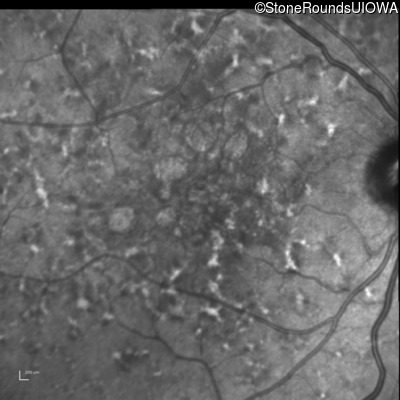

Infrared Fundus Photograph - Right - 20/20 -1 sc

Exemplar

Infrared Fundus Photograph - Left - 20/32 sc